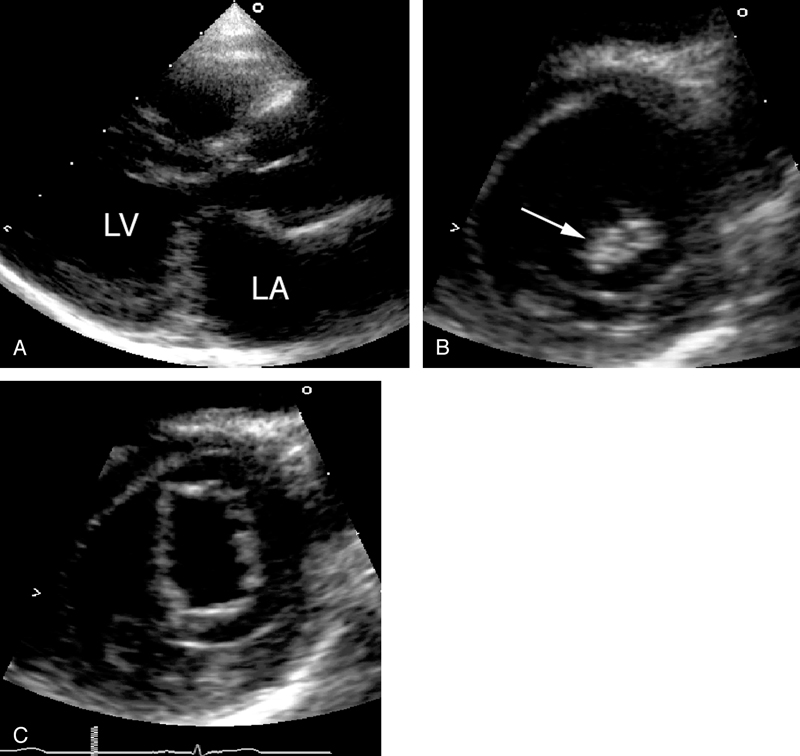

فحوصات تشخيصية لبعض امراض القلب والشرايين التاجية